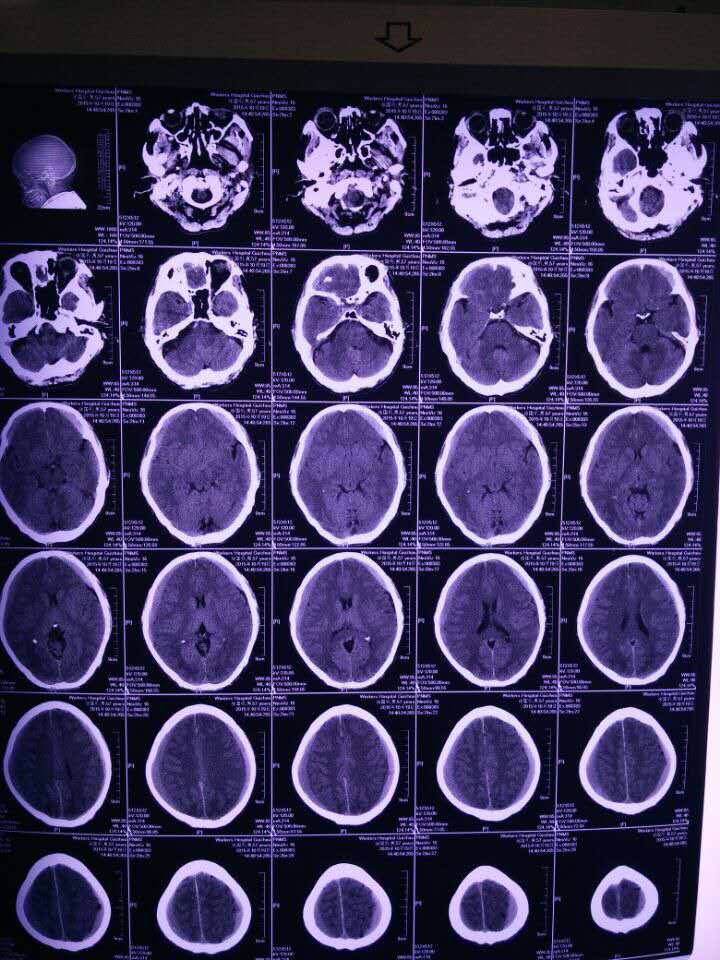

57岁,一月前头部外伤史,现轻微头痛。家属经济困难不愿意手术,请问保守用什么药好?

高渗盐大家平时怎么用的?有心衰,低钠低氯,想用泵。